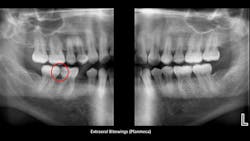

Figure 3: Extraoral bitewing radiograph showing initial caries in mandibular first and second molars

Figures 3–5 show a suggested conservative procedure when caries can be treated at the time lesions are small. Use of small, nontraumatic, round-ended burs create minimal-size preps. A 329 bur is adequate for the isthmus cut of most premolars, and a 330 should be adequate for the isthmus cut of a typical molar. Such small restorations have been shown to serve for many years when compared to larger restorations. However, unless carious lesions can be identified early in their development, tooth preparations must be larger and have been shown to have shorter service longevity.